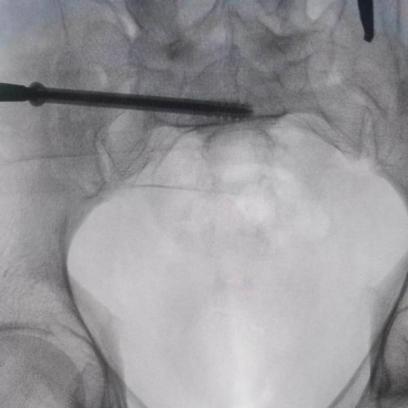

圖為透視下見(jiàn)置入的骶髂螺釘,位置、長(zhǎng)度精準(zhǔn),無(wú)絲毫偏差